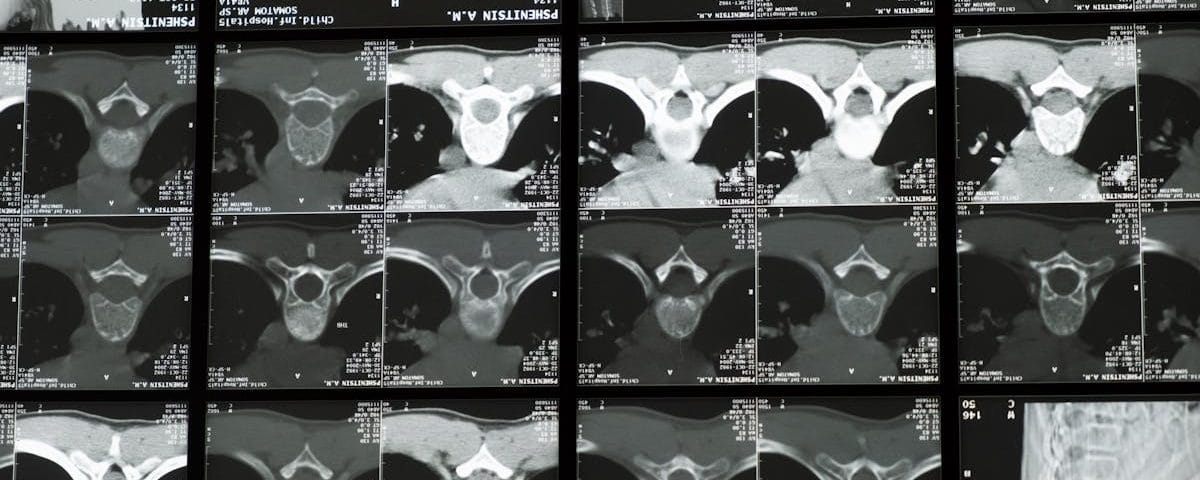

La décompression vertébrale repose sur des principes biomécaniques bien établis. Lorsqu’une pression excessive est exercée sur les disques intervertébraux, cela peut engendrer des douleurs, des bombements ou même des hernies discales. La décompression vise à créer un espace entre les vertèbres, permettant ainsi aux disques de se réhydrater et de retrouver leur forme naturelle.

Des études cliniques ont montré que cette méthode peut efficacement soulager la douleur et favoriser la régénération des tissus. En effet, en réduisant la pression sur les nerfs spinaux, la décompression neurovertébrale contribue à atténuer les symptômes associés, notamment les sensations de douleur irradiant vers les membres et les engourdissements.